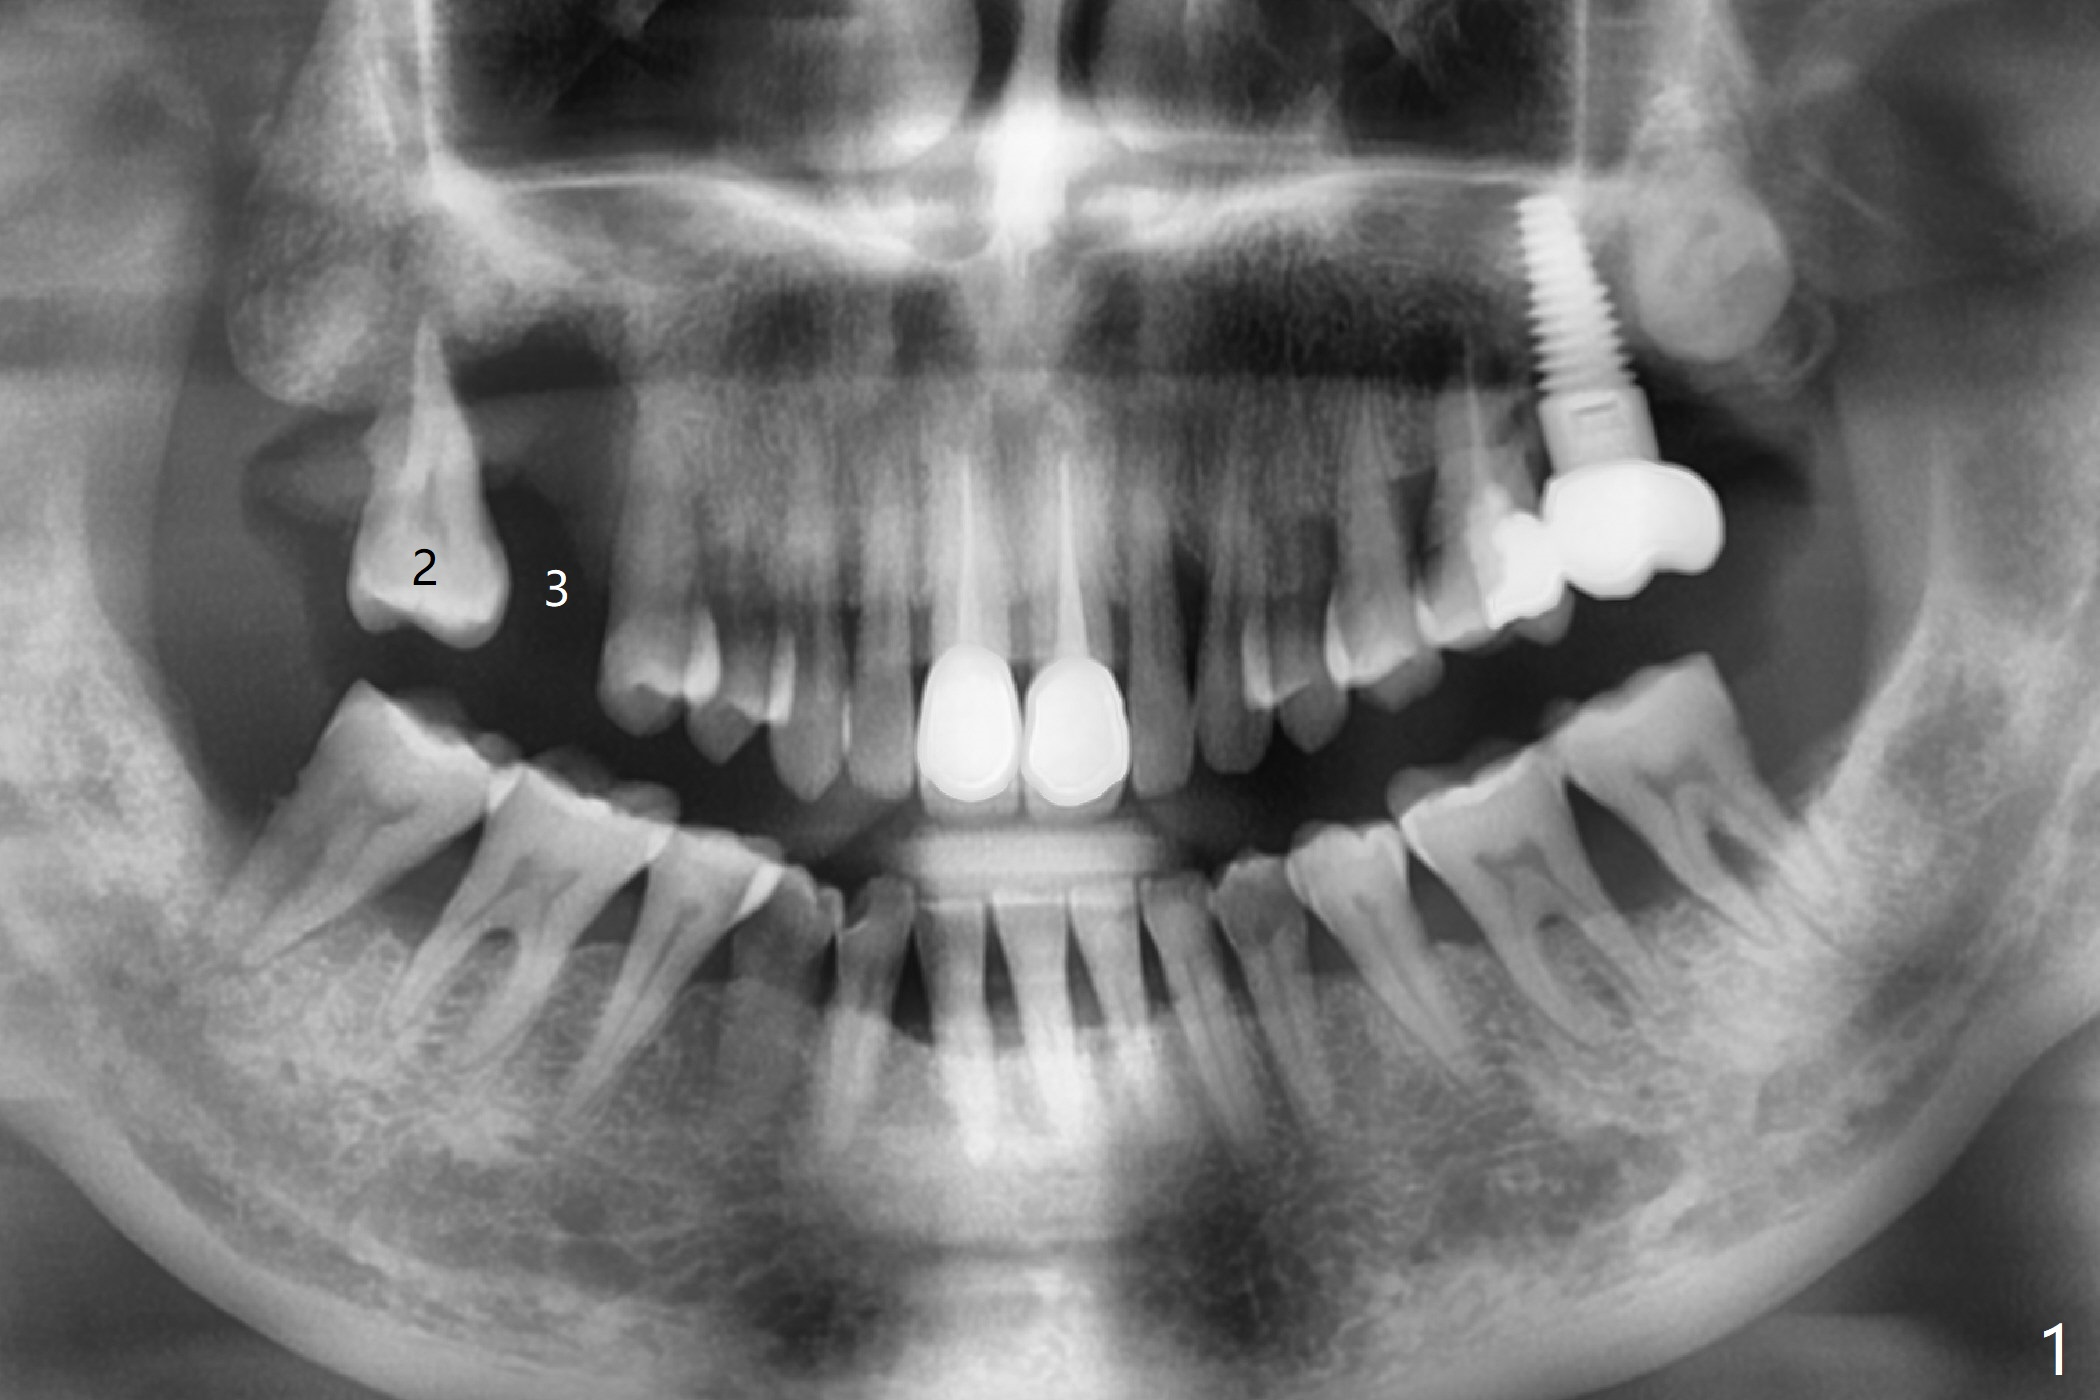

The tooth #2 of a 54-year-old woman has severe bone loss, while #3 has exfoliated (Fig.1). If the former is found without shifting, incision will be made at #3 (and prepare 4 and 6 mm tissue punches), followed by IS drills with 3 mm stoppers until 4.5 mm in diameter (Fig.3). Sinus lift will be accomplished with 3.6 mm round drill from Master Kit with 4-6 mm stoppers, followed by PRF membrane (total 3-4) and Vanilla Graft. Use Prosthetic Planning Kit to choose a proper cementation abutment. The tooth #2 will be extracted. Osteotomy starts with 7 mm stopper (Fig.2,3)...